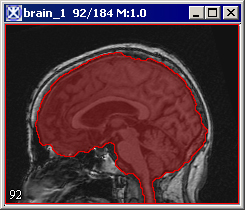

Paints the extracted brain onto the current image. See also Figure 3.

Figure 3. The Extract Brain to Paint option: on your left is the original image and on your right is the result image with the brain extracted to paint.